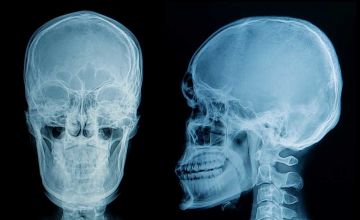

Telerradiografia

Uma telerradiografia, também conhecida como radiografia cefalométrica, é um exame de imagem utilizado principalmente na área da ortodontia. É um tipo especial de radiografia que fornece uma visão frontal e lateral da cabeça e do crânio, permitindo uma avaliação detalhada das estruturas esqueléticas faciais.